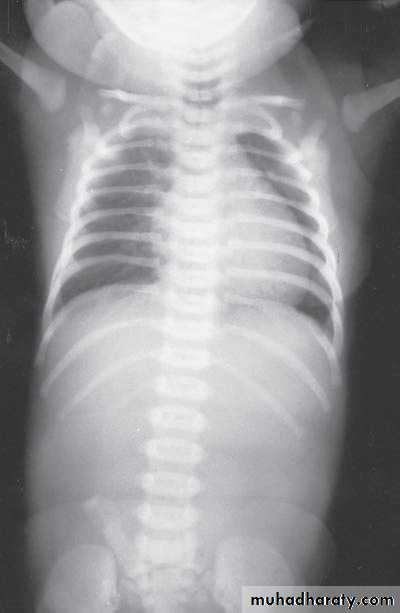

Bowel Obstruction